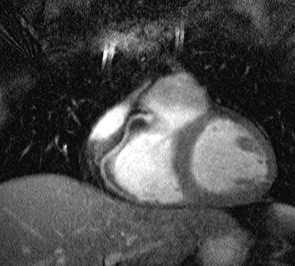

inspiration for subsequent scans. Two corresponding images

of the RCA of one volunteer are shown below.

Figure 3. The RCA of one healthy volunteer for end-expiration

(left) and inspiration (20mm shift of the right hemidiaphragm) (right).